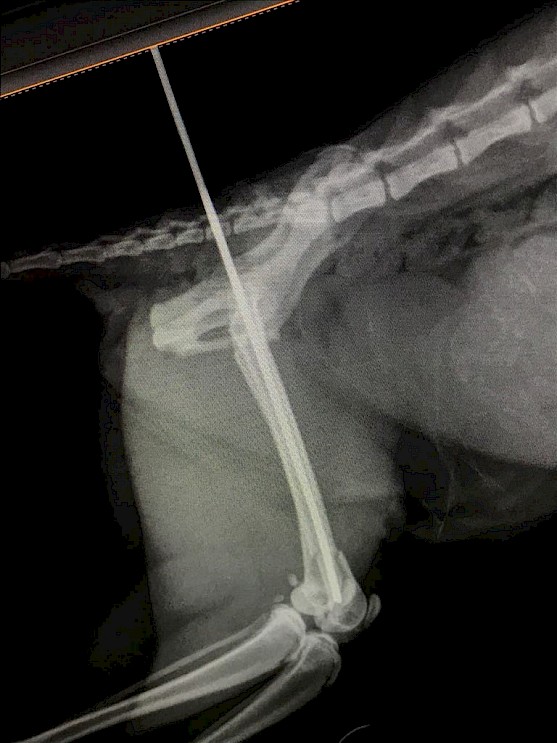

Fractures of the femur are some of the most common fractures seen in cats usually the result of major trauma. Generally, femoral fractures cause acute, non-weight bearing lameness of the affected hind leg. These fractures can occur in an immature bone or in a mature one. They can be open or closed fractures, and can be simple or multiple. For example, a 3 years old female cat was brought in the clinic due to limping in right hind leg, in appetence, lethargy, in pain upon palpation. X-ray was done and revealed fractures in the femur bone. Treatment will vary depending on the severity of the trauma. Treatment was done by doing bone pinning under general anesthesia. Antibiotic and pain killer medicines were given for a week. Try to prevent your cat from walking or moving too much. After surgical repair of the fracture, the cat will be kept restricted from activity for several weeks and the skin incision will be monitored while healing

X-ray of a femur fracture repaired with an internal fixation device made from pins and an acrylic cement.